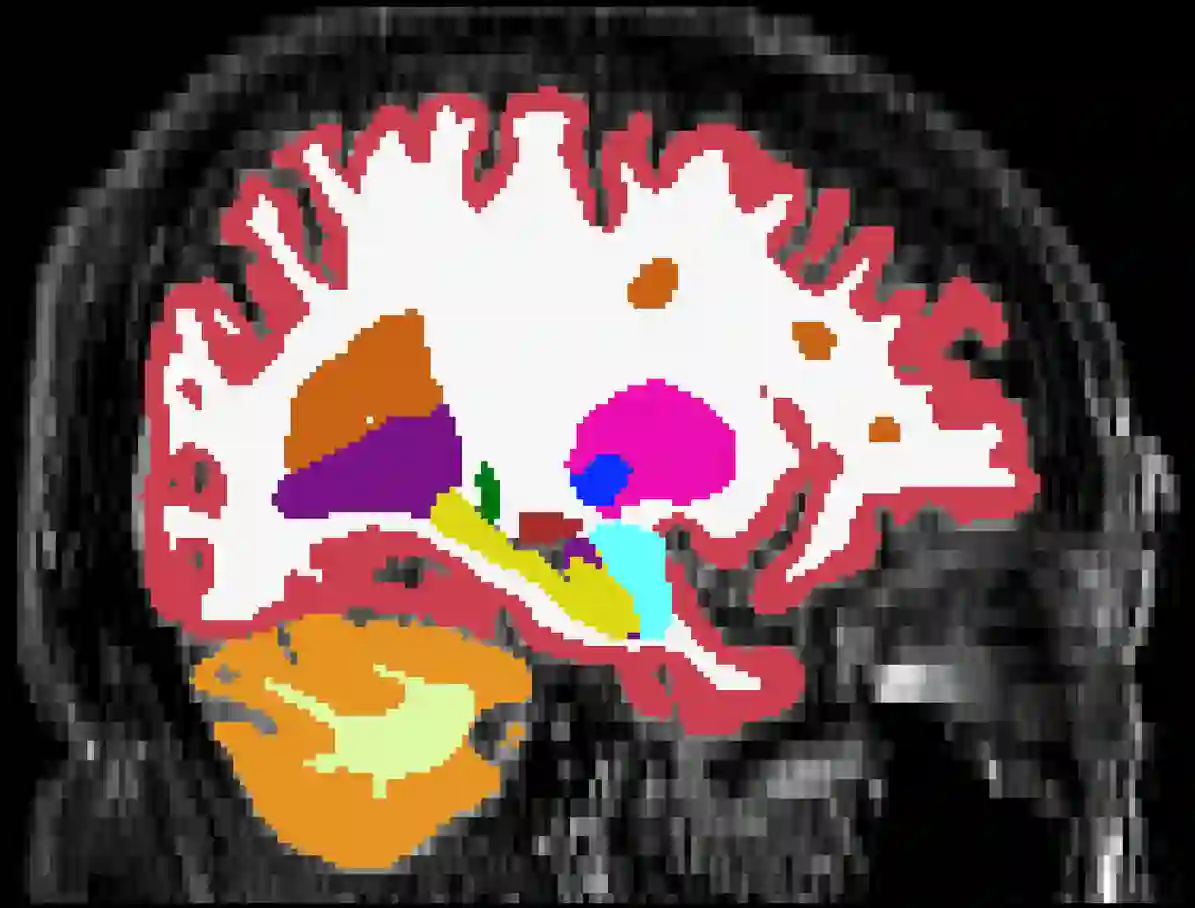

Brain atrophy and white matter hyperintensity (WMH) are critical neuroimaging features for ascertaining brain injury in cerebrovascular disease and multiple sclerosis. Automated segmentation and quantification is desirable but existing methods require high-resolution MRI with good signal-to-noise ratio (SNR). This precludes application to clinical and low-field portable MRI (pMRI) scans, thus hampering large-scale tracking of atrophy and WMH progression, especially in underserved areas where pMRI has huge potential. Here we present a method that segments white matter hyperintensity and 36 brain regions from scans of any resolution and contrast (including pMRI) without retraining. We show results on six public datasets and on a private dataset with paired high- and low-field scans (3T and 64mT), where we attain strong correlation between the WMH ($\rho$=.85) and hippocampal volumes (r=.89) estimated at both fields. Our method is publicly available as part of FreeSurfer, at: http://surfer.nmr.mgh.harvard.edu/fswiki/WMH-SynthSeg.